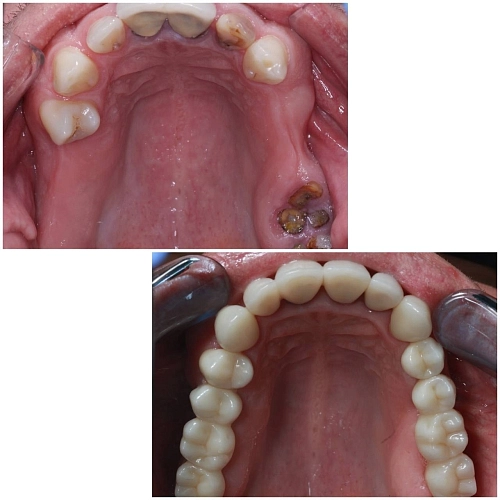

Клинический случай:

У пациента значительная потеря зубов, что привело к изменению прикуса и функциональным нарушениям.

1. Лечение зубов: На первоначальном этапе была проведена санация полости рта. Удалены не подлежащие восстановлению зубы, проведены процедуры по лечению кариеса и подготовке оставшихся зубов к дальнейшему лечению. Это создало оптимальные условия для последующих ортопедических и ортодонтических вмешательств.

4. Тотальное протезирование: После завершения ортодонтического этапа и интеграции имплантов было проведено тотальное протезирование с поднятием высоты прикуса. Это позволило восстановить функциональные и эстетические параметры.